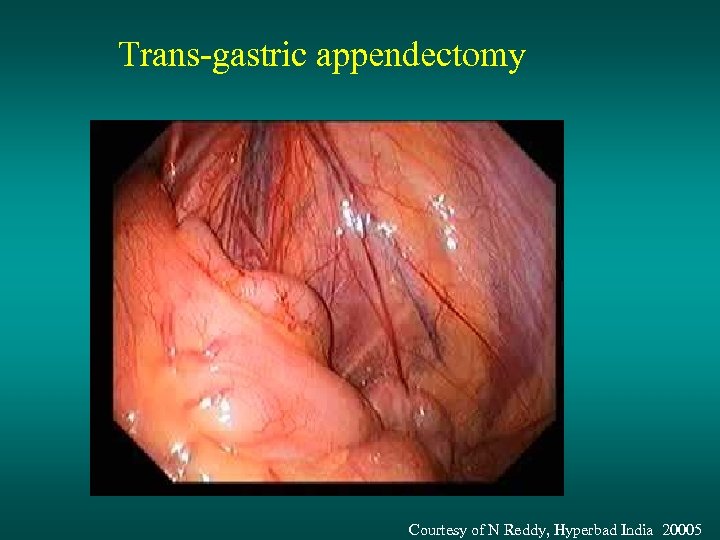

Trans-gastric appendectomy Courtesy of N Reddy, Hyperbad India 20005

Trans-gastric appendectomy Courtesy of N Reddy, Hyperbad India 20005